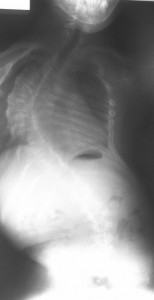

Twisted Spine And Rotated Vertebrae - Back And Neck Pain

Learn more about rotated vertebrae and how best to protect you back. One way to hurt your back is to lift with a twisted spine. Spinal Rotation and Scoliosis. Scoliosis is often called a lateral curve of the spine, ... Read Article